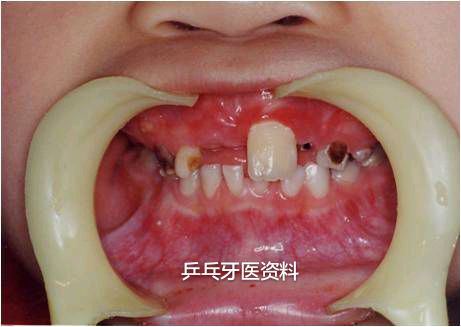

2.前牙拥挤不齐